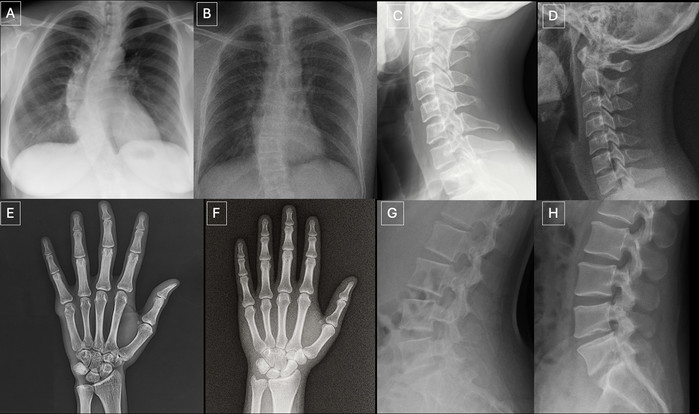

| ▲ 해부학적 구조에 맞춰 촬영한 실제 방사선 사진과 GPT-4o로 생성한 방사선 사진 비교: (A) 실제 흉부 전후면 방사선 사진, (B) GPT-4o로 생성한 후전면 흉부 방사선 사진, (C) 실제 경추 측면 방사선 사진, (D) GPT-4o로 생성한 경추 측면 방사선 사진, (E) 실제 손 전후면 방사선 사진, (F) GPT-4o로 생성한 손 후전면 방사선 사진, (G) 실제 요추 측면 방사선 사진, (H) GPT-4o로 생성한 요추 측면 방사선 사진. 이 사진들은 GPT-4o가 다양한 해부학적 부위에서 방사선학적으로 타당한 이미지를 생성할 수 있음을 보여준다. (출처:Mar 24 2026 / The Rise of Deepfake Medical Imaging: Radiologists’ Diagnostic Accuracy in Detecting ChatGPT-generated Radiographs / Radiology) |